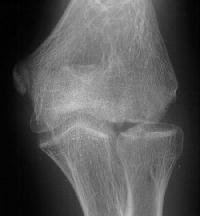

Five years later, he has limited motion (E/F 35/100) and painful clicking with elbow flexion and extension.

Plain films show humeral osteophytes and posttraumatic changes of the capitellum and radial head.